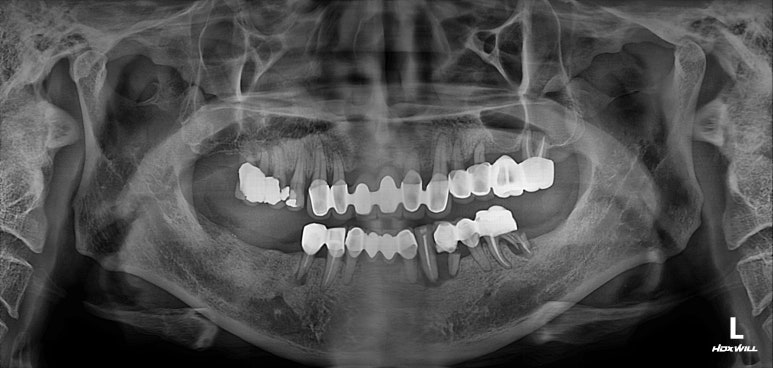

모든 최종 보철물을 연결하고 나서 치과용 파노라마 사진입니다.

정말 깔끔하게 제작된 것을 보시 수 있을겁니다.

'미적 기준'은 보편적인 측면이 있습니다. 뭔가 나란하고 비율이 대칭인 임플란트는, 잘 모르는 사람이 봐도 잘 되었구나~~ 라고 생각하게 만들어주죠 ^^

제가 가진 수술 경험을 비롯한 노하우와, 오스템 임플란트의 네비게이션 임플란트 시스템이 합작해낸 결과물!